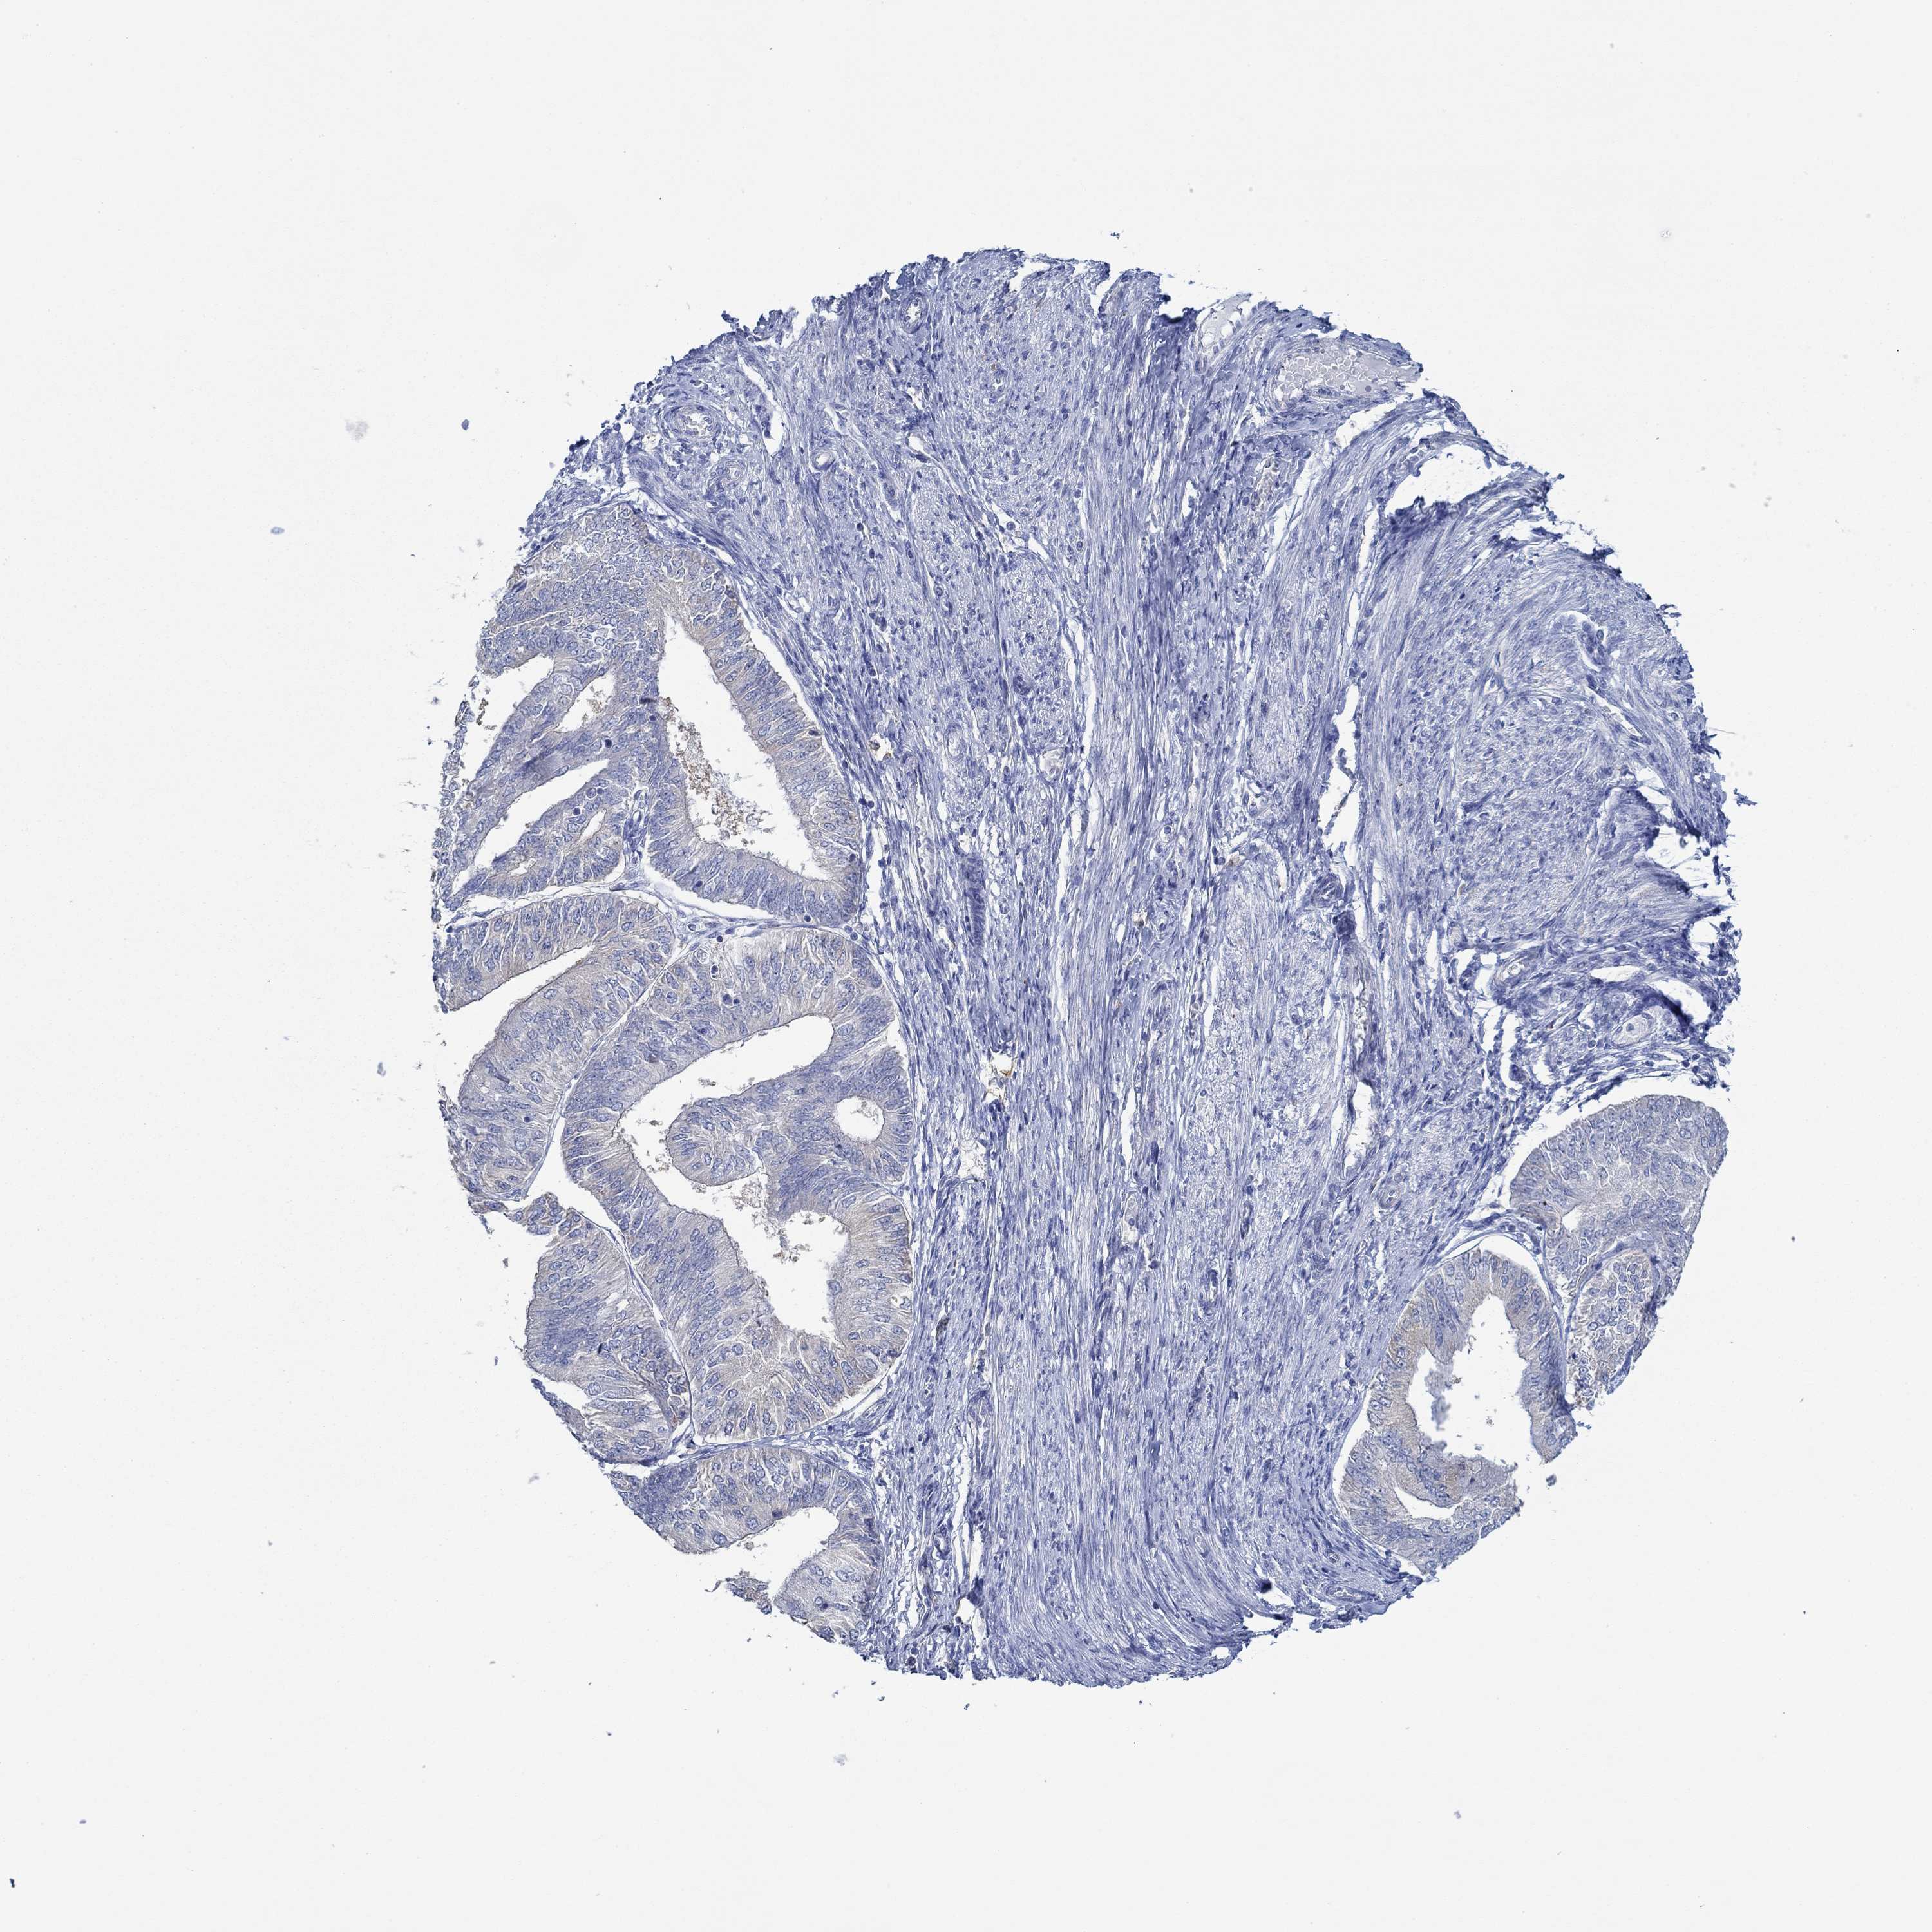

ENDOMETRIAL CANCER - Protein expressioni

A mouse-over function shows sample information and annotation data. Click on an image to view it in a full screen mode. Samples can be filtered based on level of antibody staining by selecting one or several of the following categories: high, medium, low and not detected. The assay and annotation is described here.

Note that samples used for immunohistochemistry by the Human Protein Atlas do not correspond to samples in the TCGA dataset.

Antibody stainingi

Antibody staining in the annotated cell types in the current human tissue is reported as not detected, low, medium, or high, based on conventional immunohistochemistry profiling in selected tissues. This score is based on the combination of the staining intensity and fraction of stained cells.

Each image is clickable and will lead to virtual microscopy that enables deeper exploration of all samples and also displays staining intensity scores, fraction scores and subcellular localization as well as patient and tissue information for each sample.

Antibody HPA067508

Antibody CAB080514

Antibody CAB080517